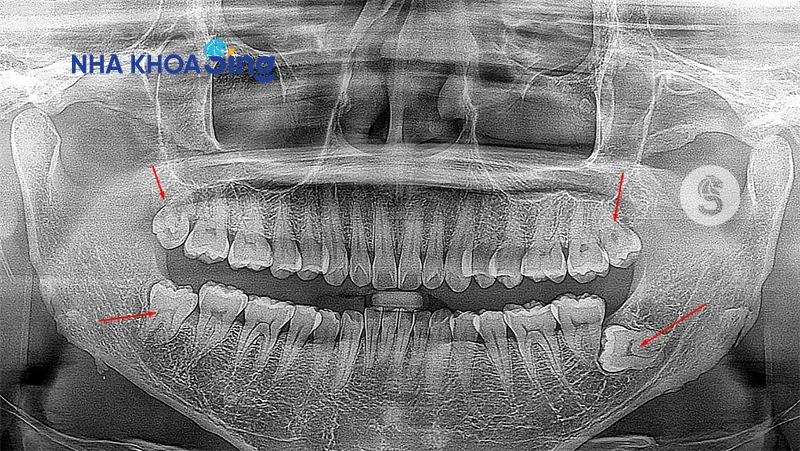

Hình ảnh 4 chiếc răng khôn trong cung hàm người trưởng thành, được nhìn thấy qua phim Xquang

Do vậy, một người trưởng thành có thể có tối đa 4 chiếc răng khôn, tuy nhiên không phải ai cũng mọc đủ, thậm chí có người cả đời không mọc chiếc răng khôn nào.